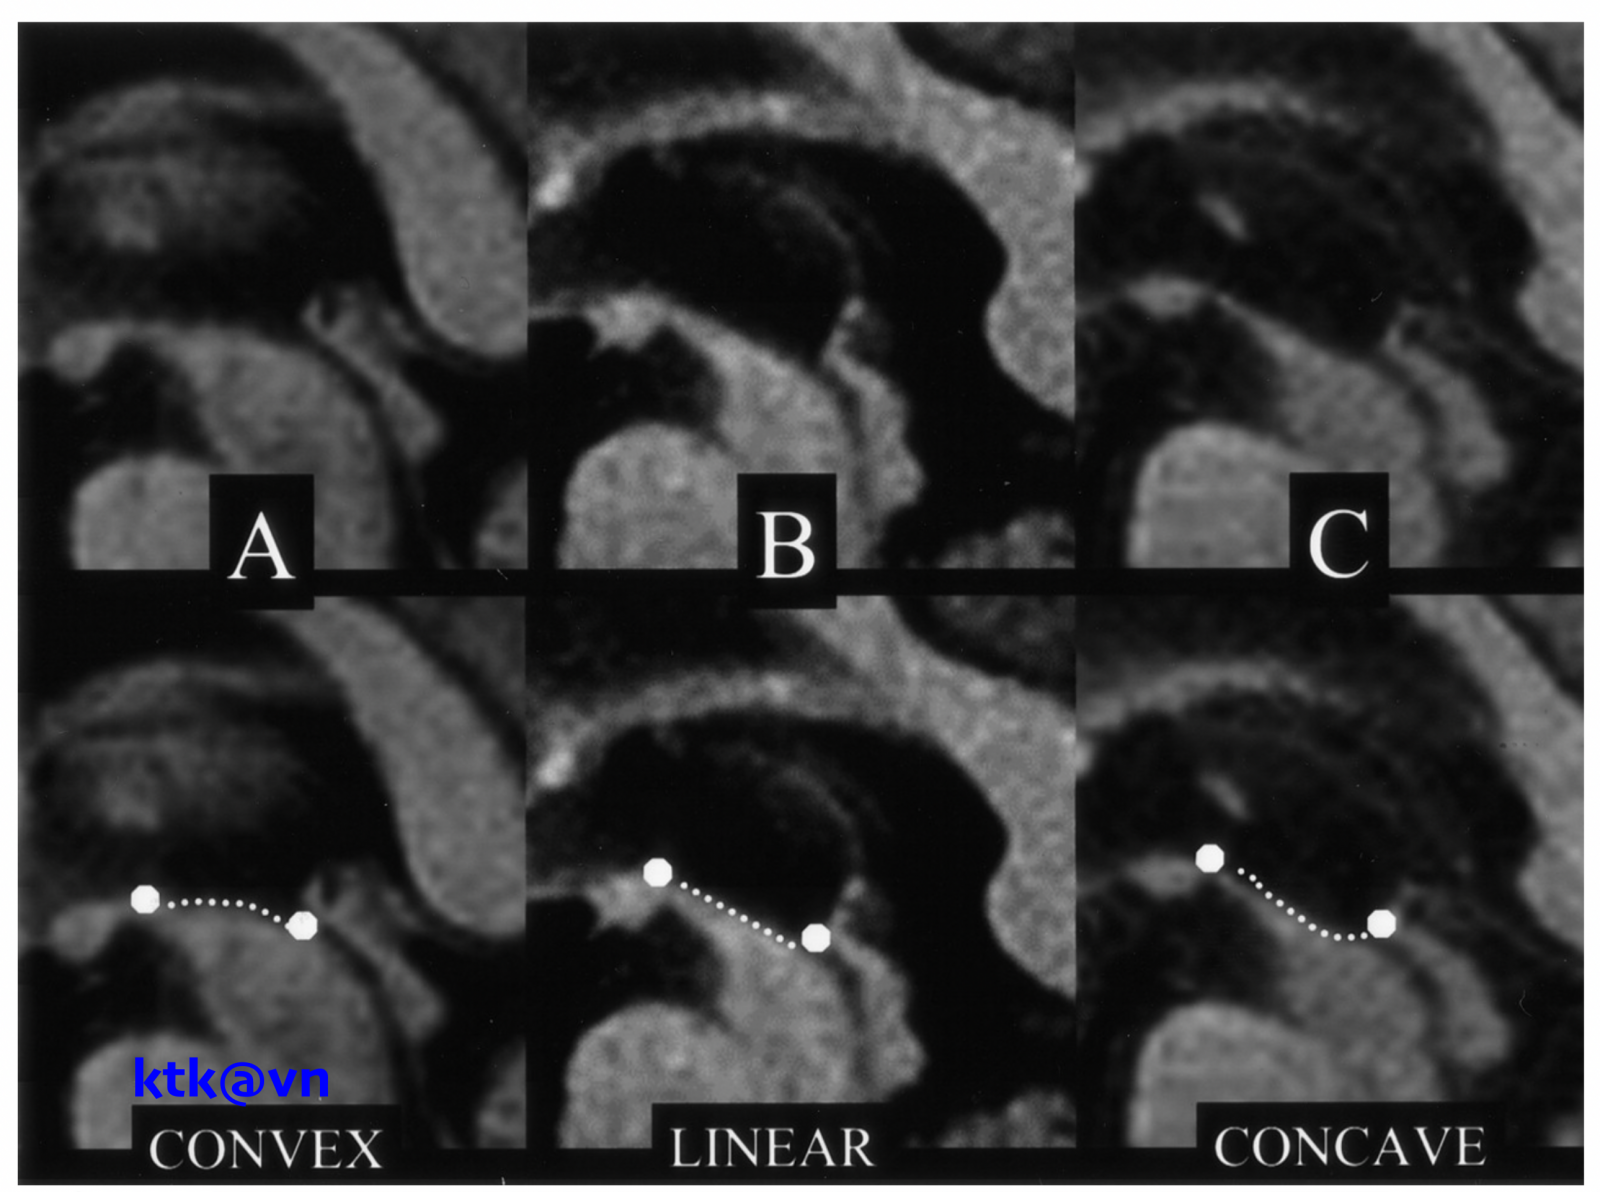

Những đặc điểm thường gặp trên hình ảnh phim chụp cộng hưởng từ sọ não là teo não giữa, giãn não thất ba, teo cuống tiểu não trên (SCP), teo thùy trán và thái dương. Teo não giữa được thể hiện trực quan qua hình ảnh “mỏ chim ruồi” khi nhìn trên lát cắt đứng dọc, hình ảnh “chuột Mickey” khi nhìn trên lát cắt ngang, hình ảnh “morning glory” (một số tài liệu gọi là dấu hiệu hoa mòng biển) trên lát cắt ngang. Teo cuống tiểu não trên, dấu hiệu “chim ruồi”, dấu hiệu “hoa mòng biển” trên cộng hưởng từ cấu trúc có độ đặc hiệu cao nhưng độ nhạy kém hơn tiêu chuẩn lâm sàng.